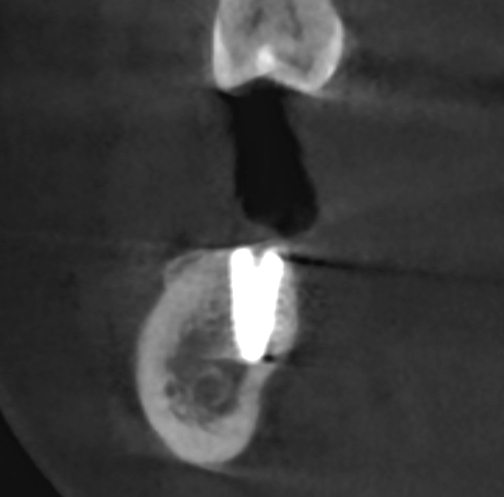

Ryc. 12. Skan tomografii stożkowej w okolicy 45, w 10 dobie po zabiegu.

Ryc. 20. Skan w płaszczyźnie horyzontalnej ukazuje regenerację blaszki korowej przedsionkowej